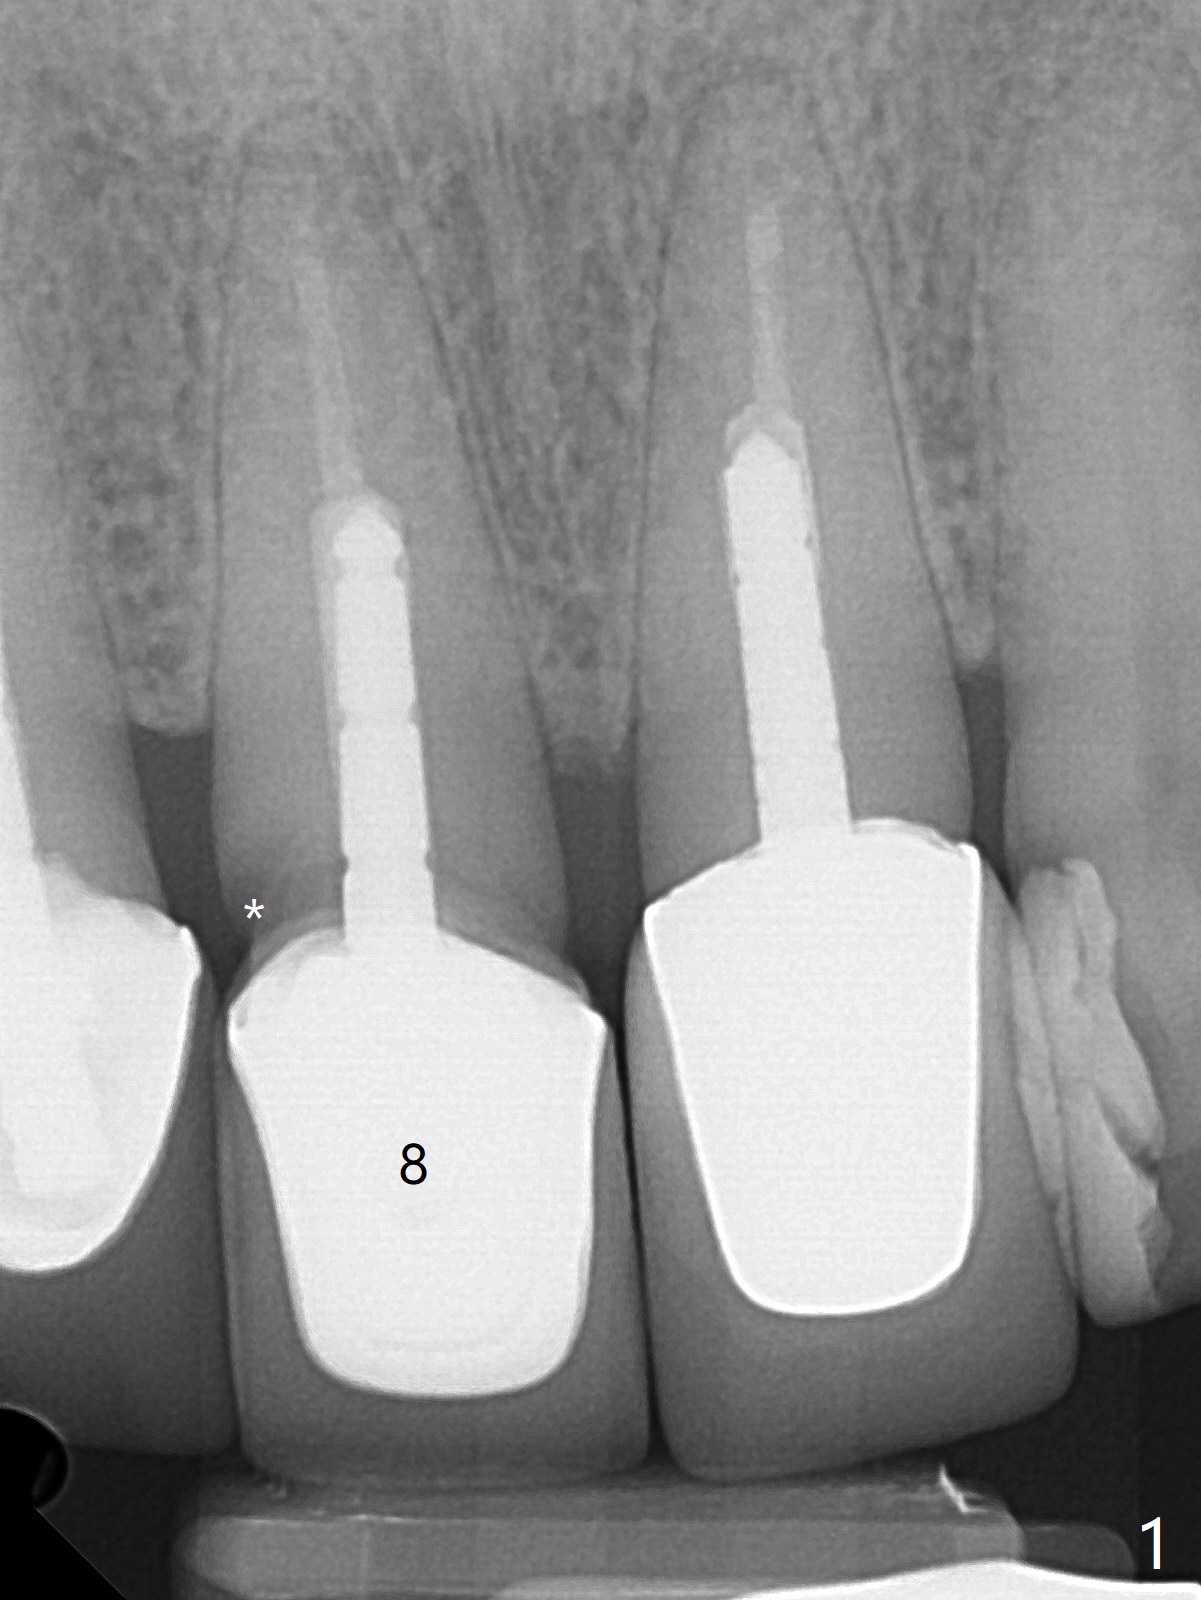

A 66-year-old man returns to clinic for #8 crown redo because of marginal leakage (Fig.1 *). After crown and caries removal, the tooth requires crown lengthening or basically non salvageable (Fig.2,3). For untold reasons, gingivectomy is performed with Waterlase without topical or local anesthesia. Hemostasis is excellent for impression, although there is wide spread of tissue debris from laser (Fig.4 >). The gingiva heals 4 weeks (Fig.5) and 6 weeks (Fig.6) postop.